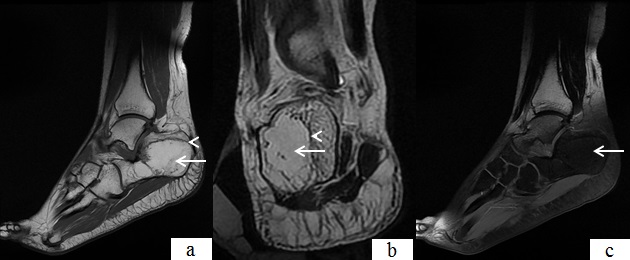

Le lipome intraosseux est une tumeur bénigne rare représentant 0,1% de l'ensemble des tumeurs squelettiques. Au membre inférieur, sa localisation au calcanéum est retrouvée dans 15% des cas. Son étiopathogénie demeure imprécise et reste partagée entre origine tumorale bénigne et post-traumatique. Elle touche avec légère prédominance féminine, le sujet de la quatrième ou cinquième décade. La clinique dénuée de toute spécificité, se limite à des douleurs mécaniques de l'arrière pied; en revanche l'imagerie et particulièrement l'IRM permet de poser avec quasi-certitude le diagnostic en objectivant une tumeur de signal typiquement graisseux. Le traitement reste partagé entre l'abstention et la chirurgie avec curetage lésionnel et greffe spongieuse dans les formes douloureuses ou comportant un risque de fracture pathologique. Nous rapportons le cas d'une jeune femme, âgée de 24 ans, présentant des douleurs de type mécanique de l'arrière pied gauche, résistantes aux traitements antalgiques et chez qui une IRM a objectivé une tumeur du calcanéum se présentant en hyper signal avec liseré périphérique d'ostéosclérose en hyposignal sur les séquences T1 et T2 et perdant son signal sur la séquence de suppression de graisse, témoignant de son caractère graisseux. Nous avons retenu le diagnostic de lipome et vue que la douleur a été intense avec retentissement sur l'activité physique, la patiente a bénéficié d'un traitement chirurgical, consistant en un curetage du produit lipomateux avec greffe spongieuse.